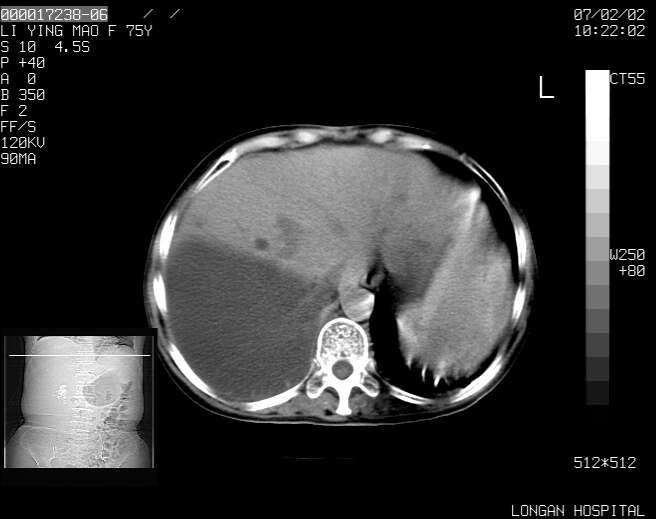

以下是引用dyqct在2007-2-10 8:53:00的发言:[br]考虑:1、肝脏多发囊肿[br] 2、左肾囊肿,右肾多发结石并积水。[br] 3、右胸少量积液。[br] 4、右肾周包裹性积液或淋巴管瘤(有见缝就钻的征象、薄隔、小结节状钙化)?[br] 5、腰椎动脉瘤样骨囊肿?[br] [br] [br]